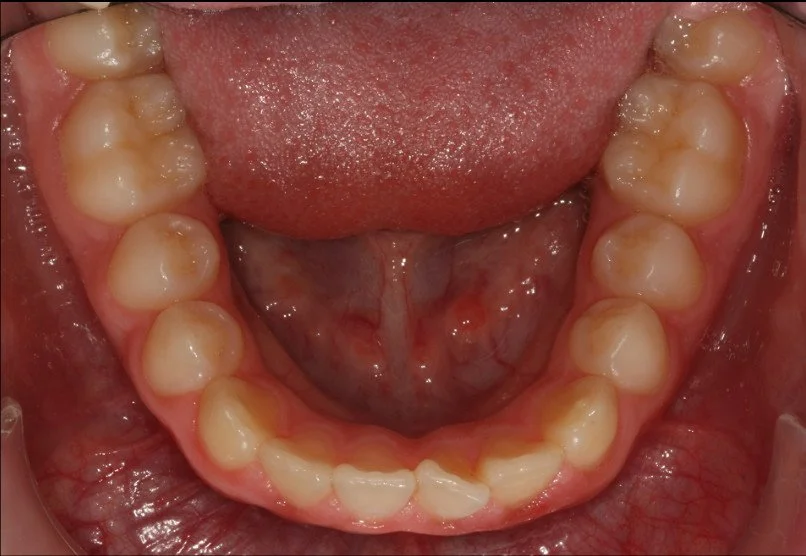

BEFORE

Trattamento con 4 estrazioni di una malocclusione di classe II con proclinazione degli incisivi superiori e inferiori.